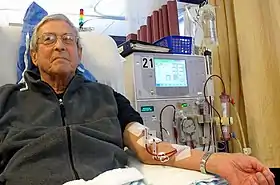

Patient receiving hemodialysis | |

In hemodialysis, the patient's blood is pumped through the blood compartment of a dialyzer, exposing it to a partially permeable membrane. The dialyzer is composed of thousands of tiny hollow synthetic fibers. The fiber wall acts as the semipermeable membrane. Blood flows through the fibers, dialysis solution flows around the outside of the fibers, and water and wastes move between these two solutions.[9] The cleansed blood is then returned via the circuit back to the body. Ultrafiltration occurs by increasing the hydrostatic pressure across the dialyzer membrane. This usually is done by applying a negative pressure to the dialysate compartment of the dialyzer. This pressure gradient causes water and dissolved solutes to move from blood to dialysate and allows the removal of several litres of excess fluid during a typical 4-hour treatment. In the United States, hemodialysis treatments are typically given in a dialysis center three times per week (due in the United States to Medicare reimbursement rules); however, as of 2005 over 2,500 people in the United States are dialyzing at home more frequently for various treatment lengths.[10] Studies have demonstrated the clinical benefits of dialyzing 5 to 7 times a week, for 6 to 8 hours. This type of hemodialysis is usually called nocturnal daily hemodialysis and a study has shown it provides a significant improvement in both small and large molecular weight clearance and decreases the need for phosphate binders.[11] These frequent long treatments are often done at home while sleeping, but home dialysis is a flexible modality and schedules can be changed day to day, week to week. In general, studies show that both increased treatment length and frequency are clinically beneficial.[12]